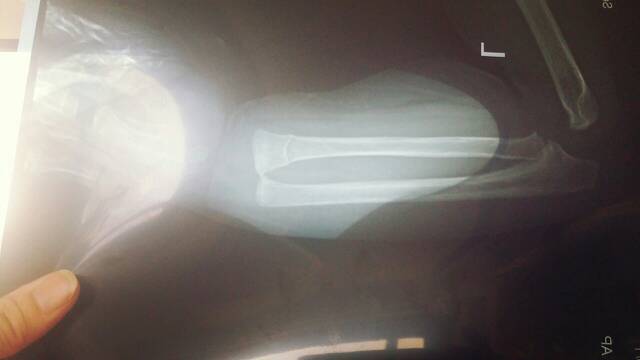

我宝宝刚满一岁,由于摔到地上了,左手先着地,左桡骨远端骨折,医生说其中一根骨头明显断了,但恢复后不会有别的问题,另一根骨头软骨有骨折迹象,有可能恢复后停止生长,导致手腕长歪,虽然可能性较小,但要到半年后才能确认。。。请有经验的医生帮我看看是否真存在这种可能性,有没有更快的方法确定后遗症,否则太折磨家人了。谢谢!